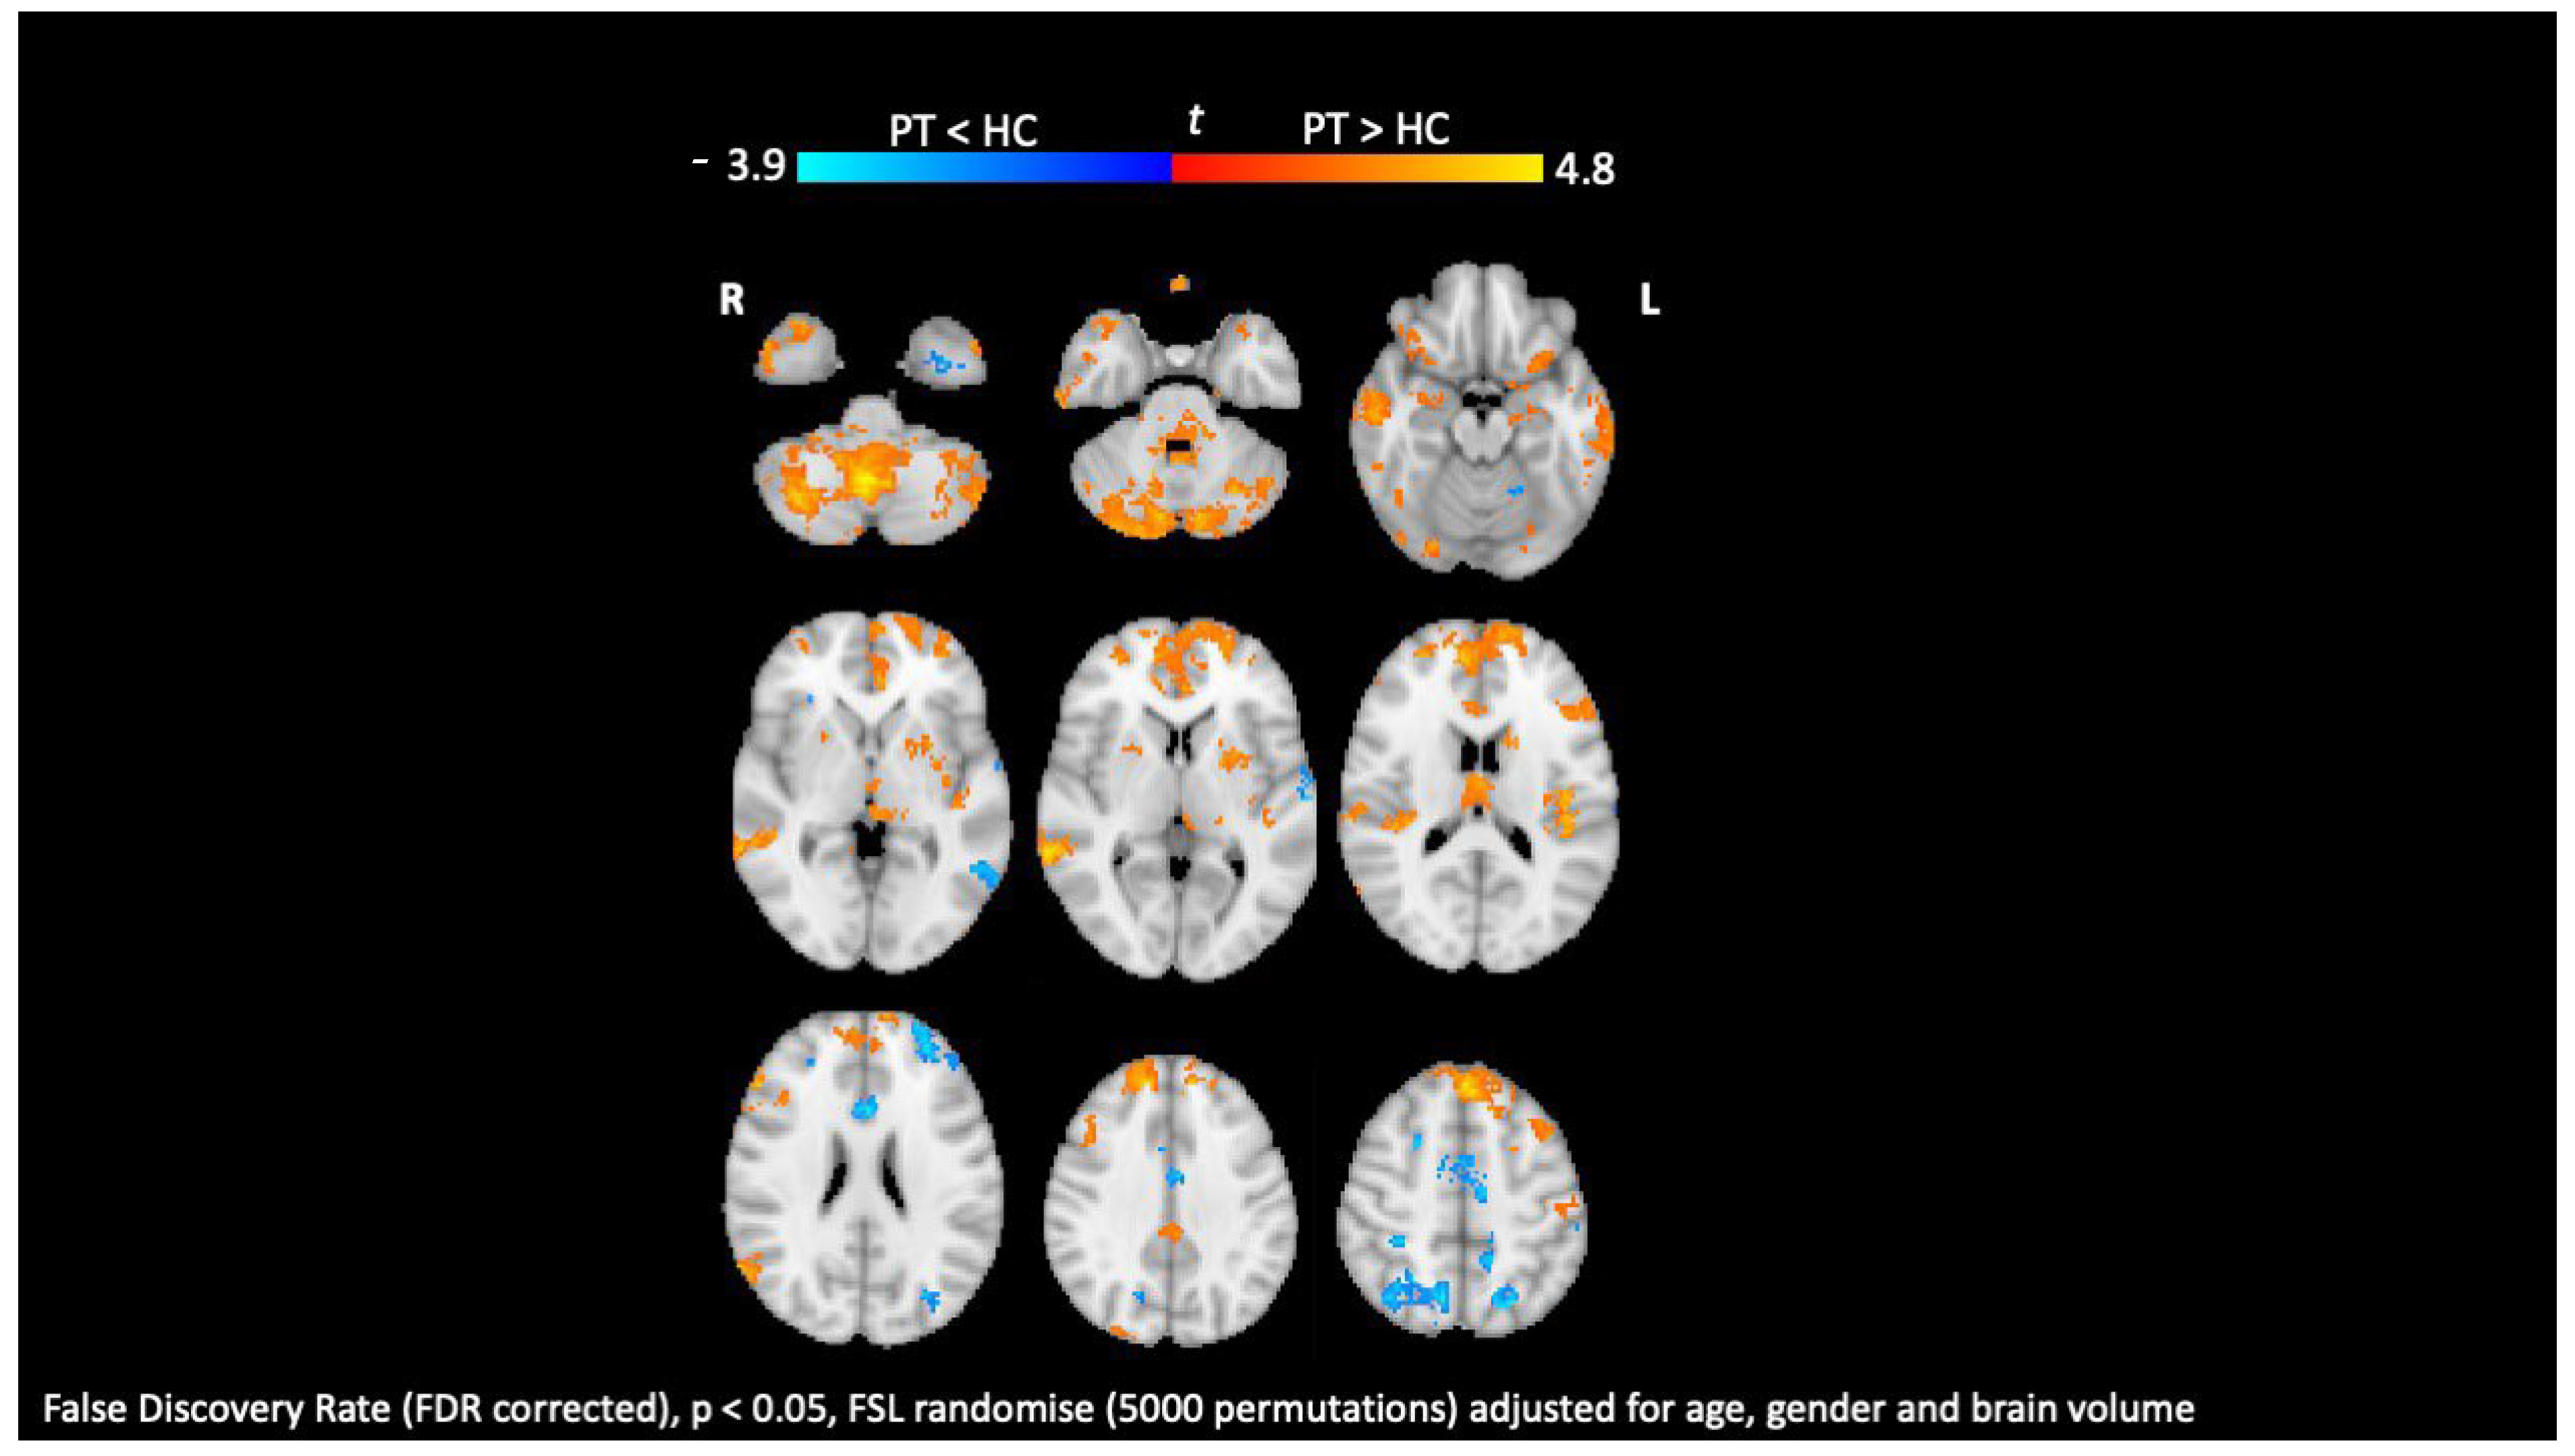

8. Diffusion Tensor Imaging

9. Functional MRI